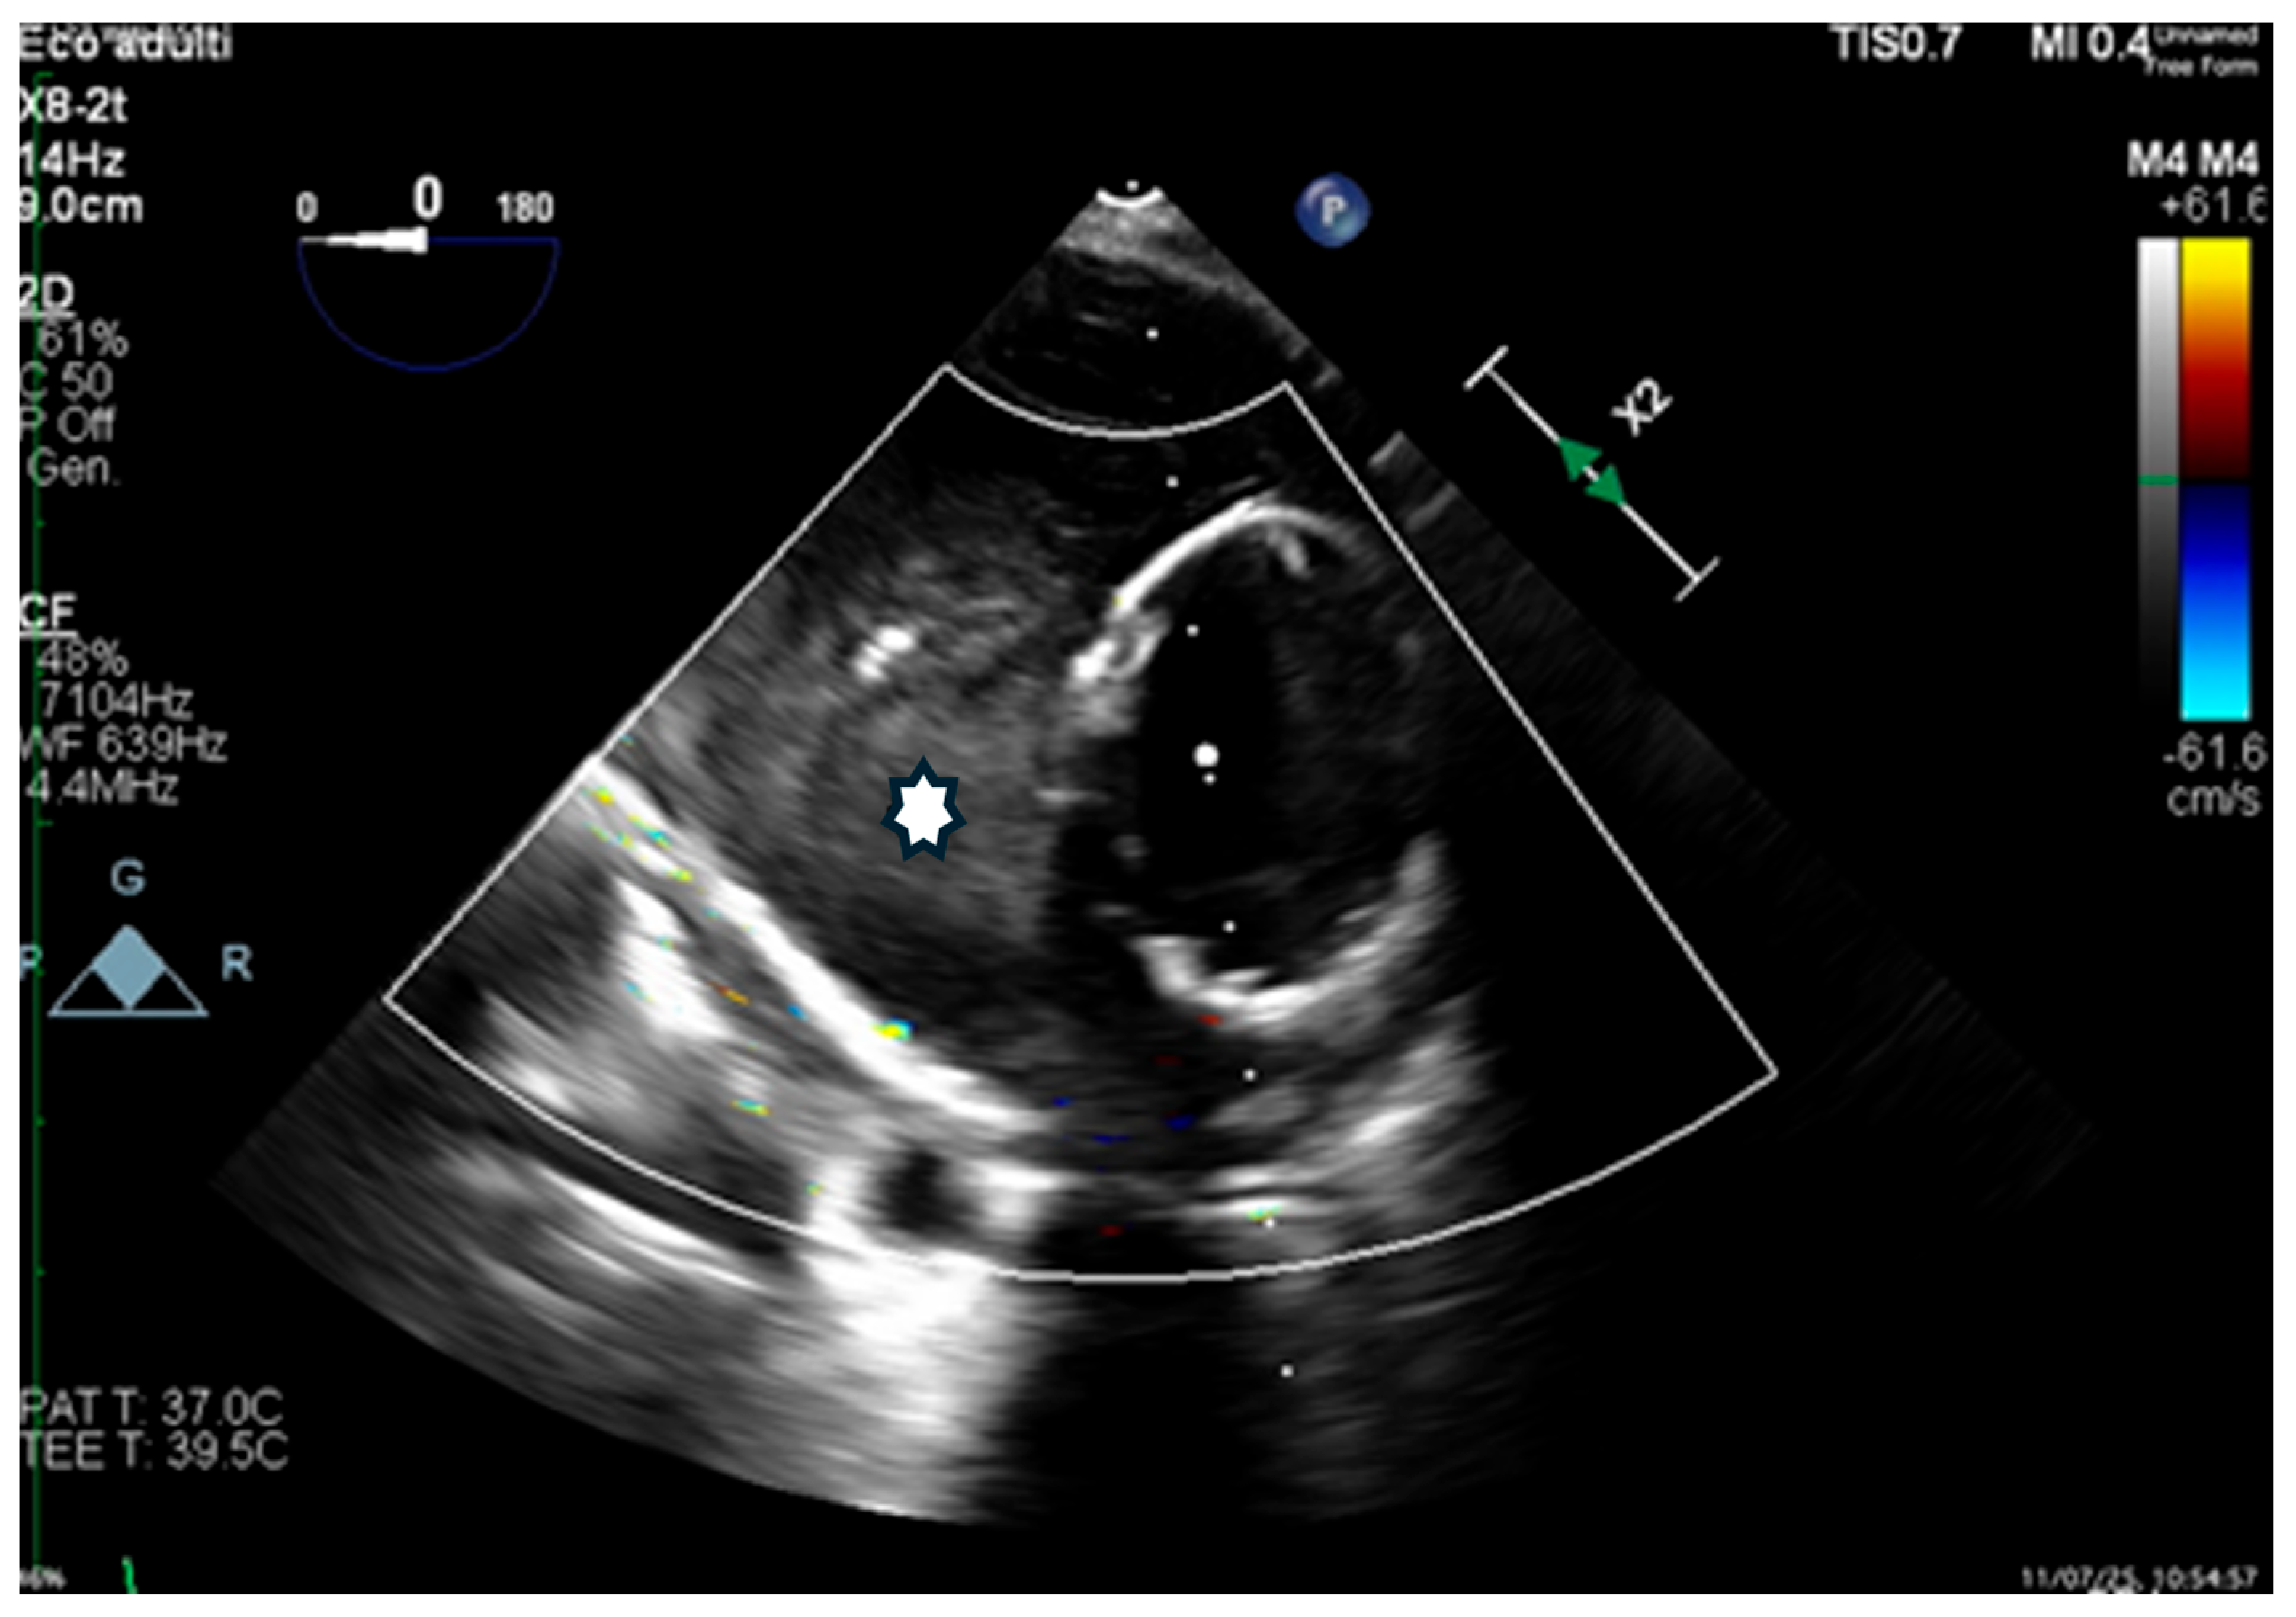

Transesophageal echocardiography (TEE) confirmed rapid thrombosis of the FL (Figure 7).

Figure 7. Transesophageal echocardiography (TEE), transverse view, showing the Terumo Aortic endograft in the true lumen and the FLOD within the false lumen, with in situ thrombosis (*).